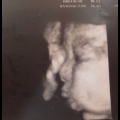

生命的期待

• 作品說明:感謝辛苦的老婆,迎接新生命的誕生是段期待又辛苦的過程,媽媽的付出和犧牲...難以言喻,未來的路,有我陪妳。